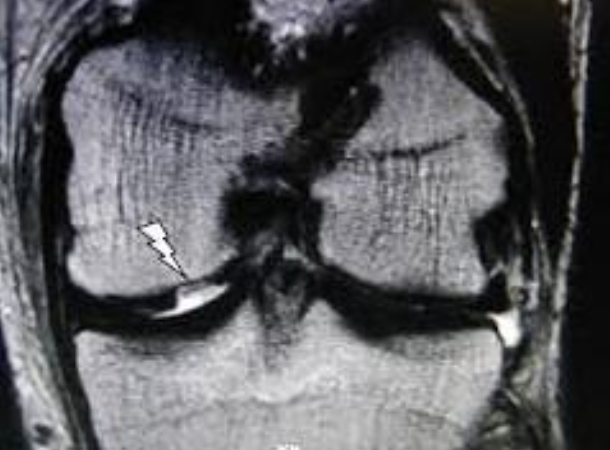

Deze defecten zijn te klein om op klassieke radiografie opgemerkt te worden . Zelfs op een MRI (scanner) is de ware diepte van het letsel niet altijd perfect te beoordelen. De beslissing om dit defect effectief te behandelen, kan daarom soms pas tijdens de ingreep (artroscopie) genomen worden.